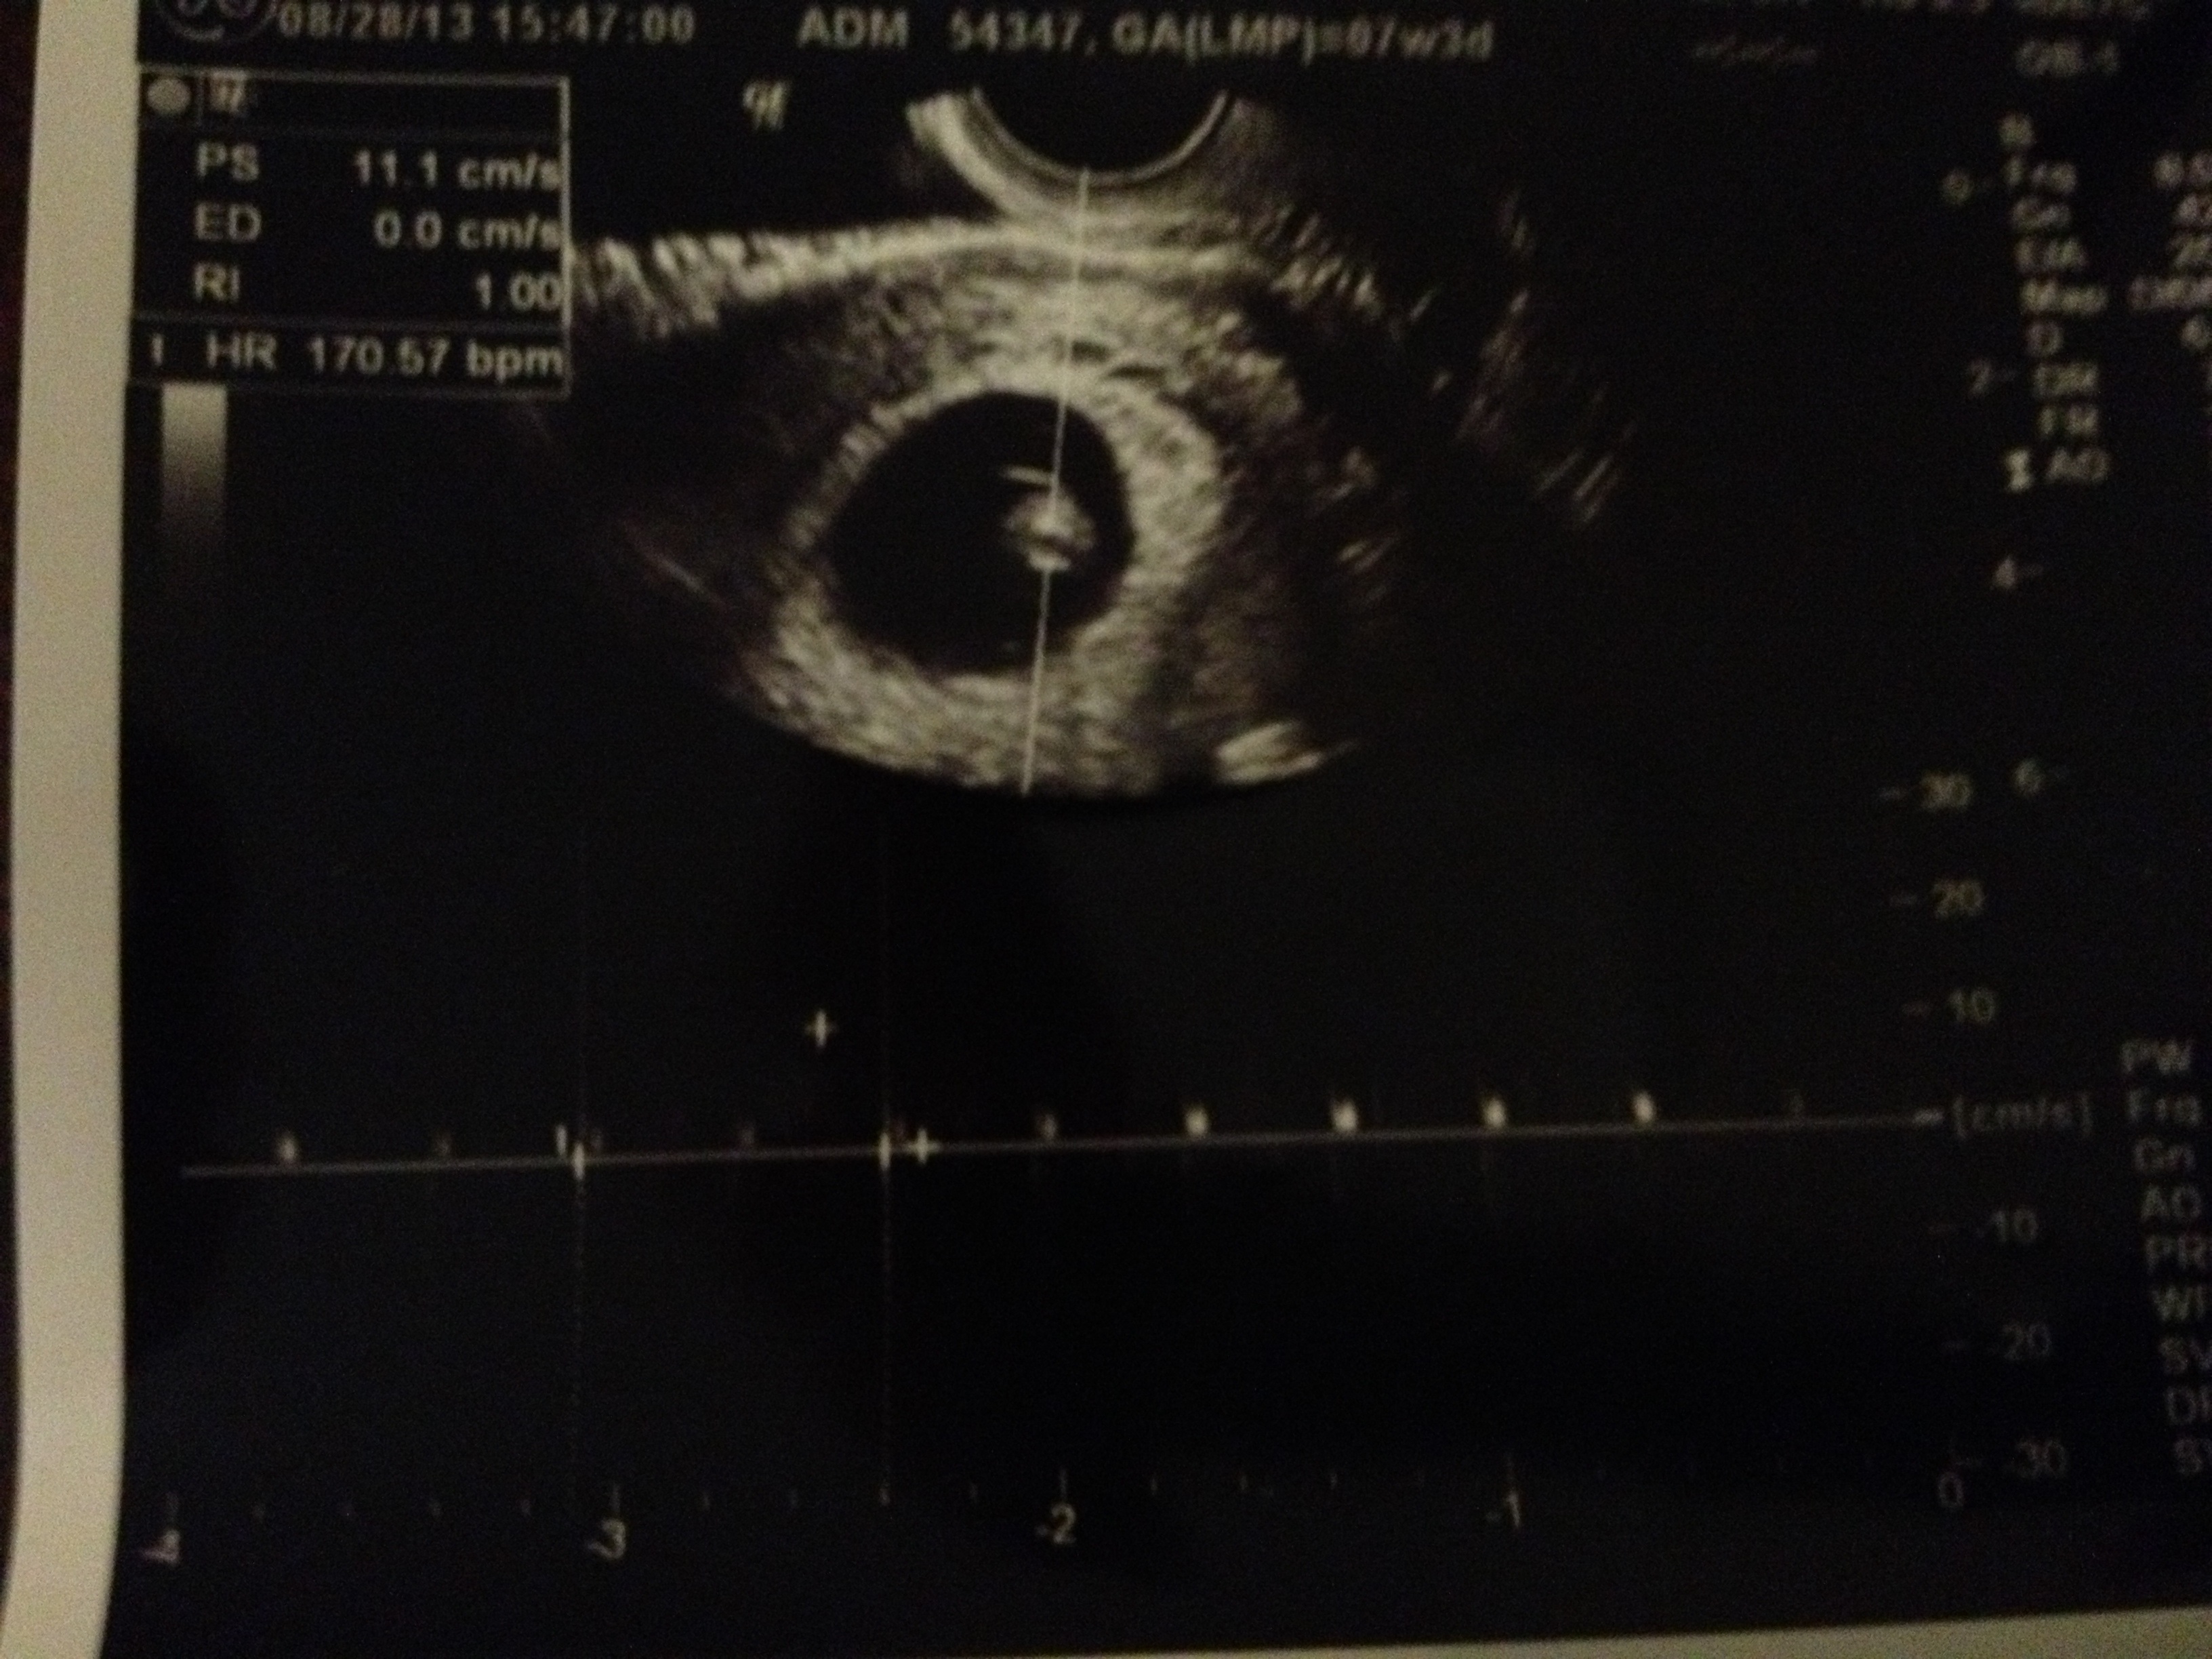

So had my first appt today and things are looking really great! Measuring 8w on the nose (ill update my ticker later) and heartbeat strong at 170! Posting from my phone so I hope the pics turn out ok.